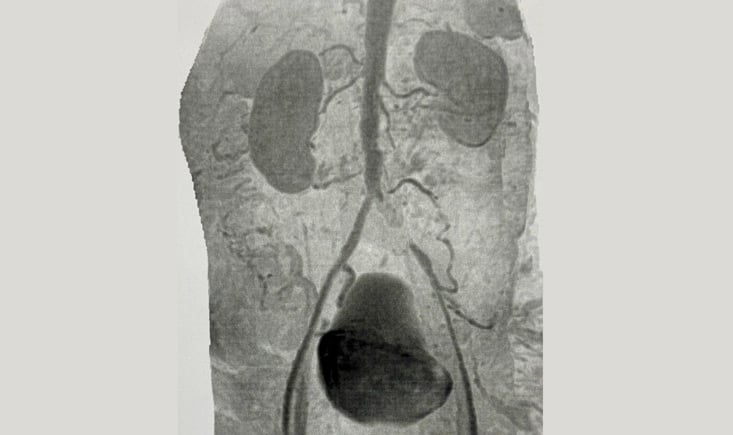

MRI: severe atheromatosis in all arterial segments with total occlusion of the left common iliac artery. Refilling of the external iliac artery by collateral and patent hypogastric artery.